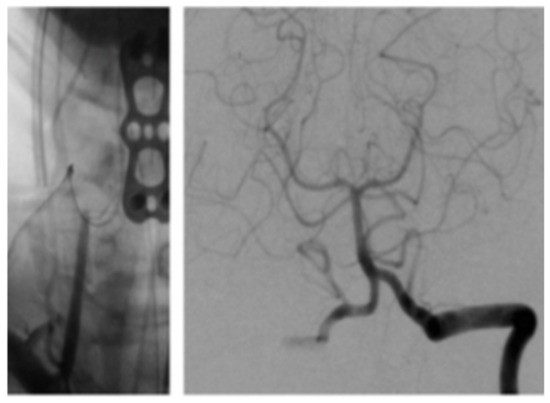

3.2. Case Illustration 2

The patient was extubated and taken to the recovery room. Her blood pressure and pulse rate were within normal range. Her neurologic exam was intact with regard to mentation, coordination and motor function. Sensory deficits were unchanged from pre-operative exam. She was taken to the angiography suite and this revealed occlusion of the right VA (Figure 6). She had a contrast brain CT 48 h later, and no evidence of ischemia or infarct was noted. She subsequently was started on Aspirin (ASA) therapy on post-op day # 3. Serial exams throughout her 5-day hospitalization remained unchanged except for improvement in pre-operative sensory deficit. Follow up angiogram 6 months later showed recanalization of right VA (Figure 7).

Figure 6. Angiogram post-op.

Figure 7. Angiogram 6 months post-op.